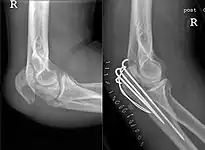

Tension band fixation

Tension band fixation is the most common form of internal fixation used for non-comminuted olecranon fractures.[5] It is typically reserved for noncomminuted fractures that are proximal to the coronoid.[2] This procedure is performed using Kirschner wire (K-wires) which converts tensile forces into compressive force.[2]